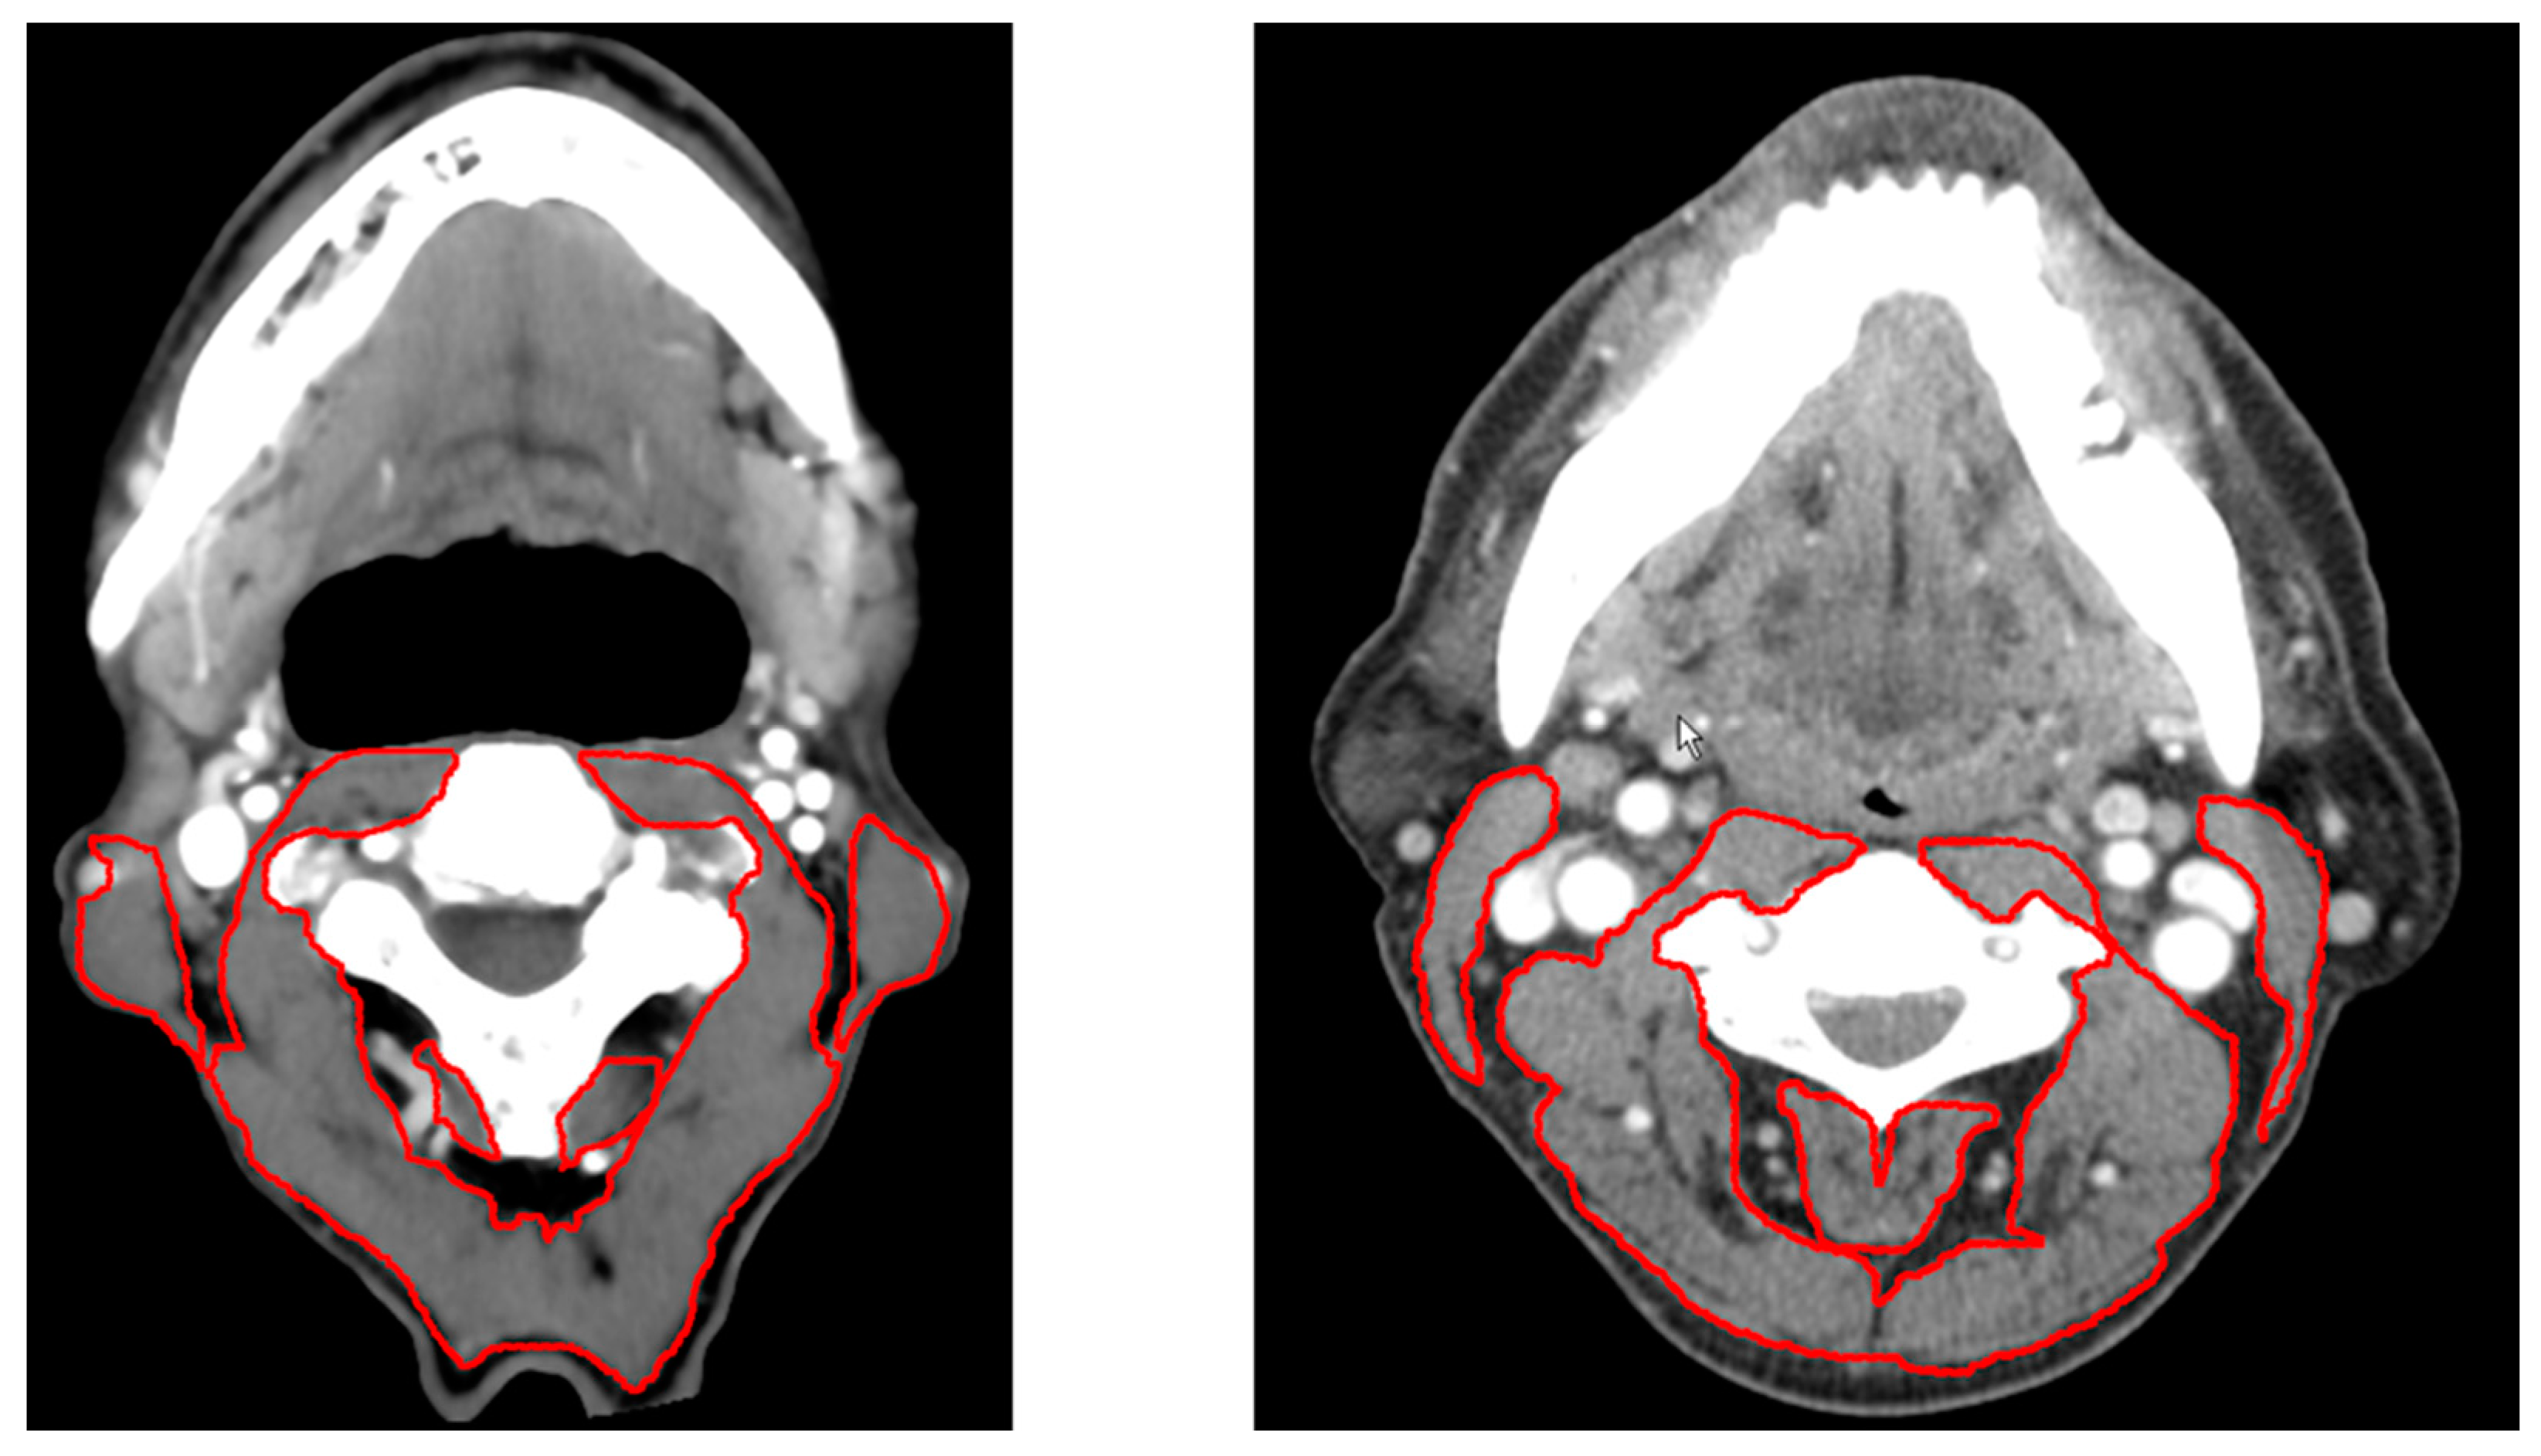

- Swartz, J.E.; Pothen, A.J.; Wegner, I.; Smid, E.J.; Swart, K.M.; de Bree, R.; Leenen, L.P.; Grolman, W. Feasibility of using head and neck ct imaging to assess skeletal muscle mass in head and neck cancer patients. Oral Oncol. 2016, 62, 28–33. [Google Scholar] [CrossRef] [PubMed]